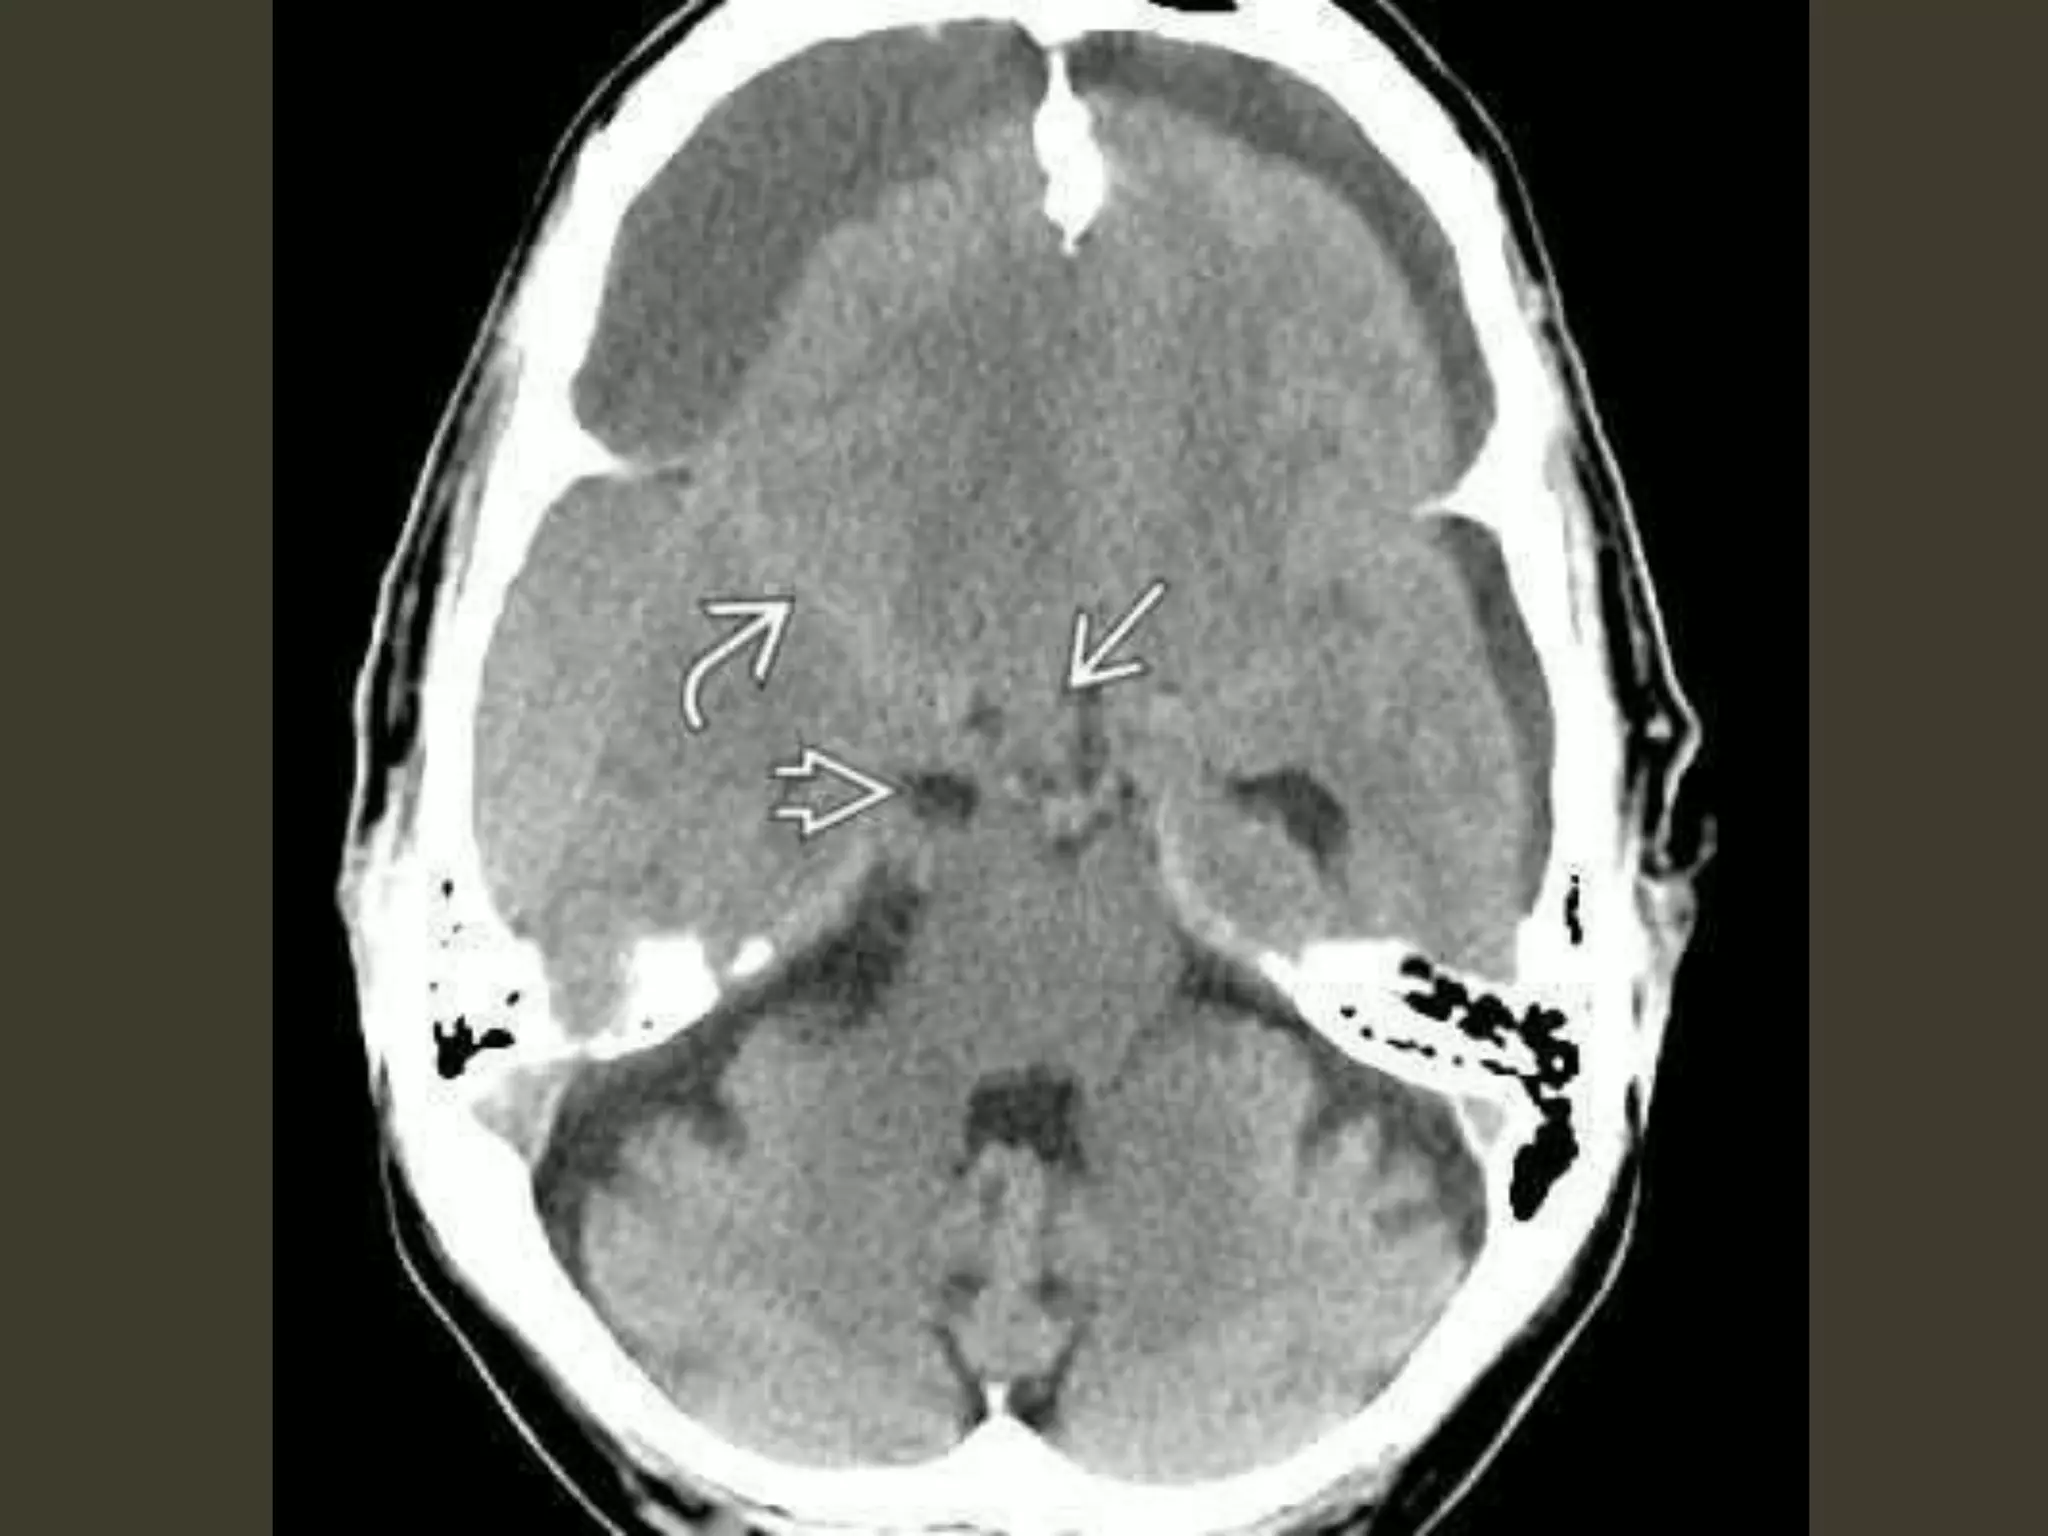

unilateral DTH: imaging

early

uncus is displaced medially

Ipsilateral aspect of the suprasellar cistern

effaced

Ipsilateral prepontine + cerebellopontine angle

cistern enlarged

Descending transtentorial

herniation

As DTH increases

hippocampus also herniates

medially

quadrigeminal cistern

compression midbrain pushed

toward the opposite side of the incisura

severe cases

entire suprasellar and quadrigeminal cisterns

are effaced.

The temporal horn can even be displaced almost

into the midline

bilateral DTH

both hemispheres become swollen

the whole central brain is flattened against the

skull base

All the basal cisterns are obliterated

hypothalamus and optic chiasm are crushed

against the sella turcica